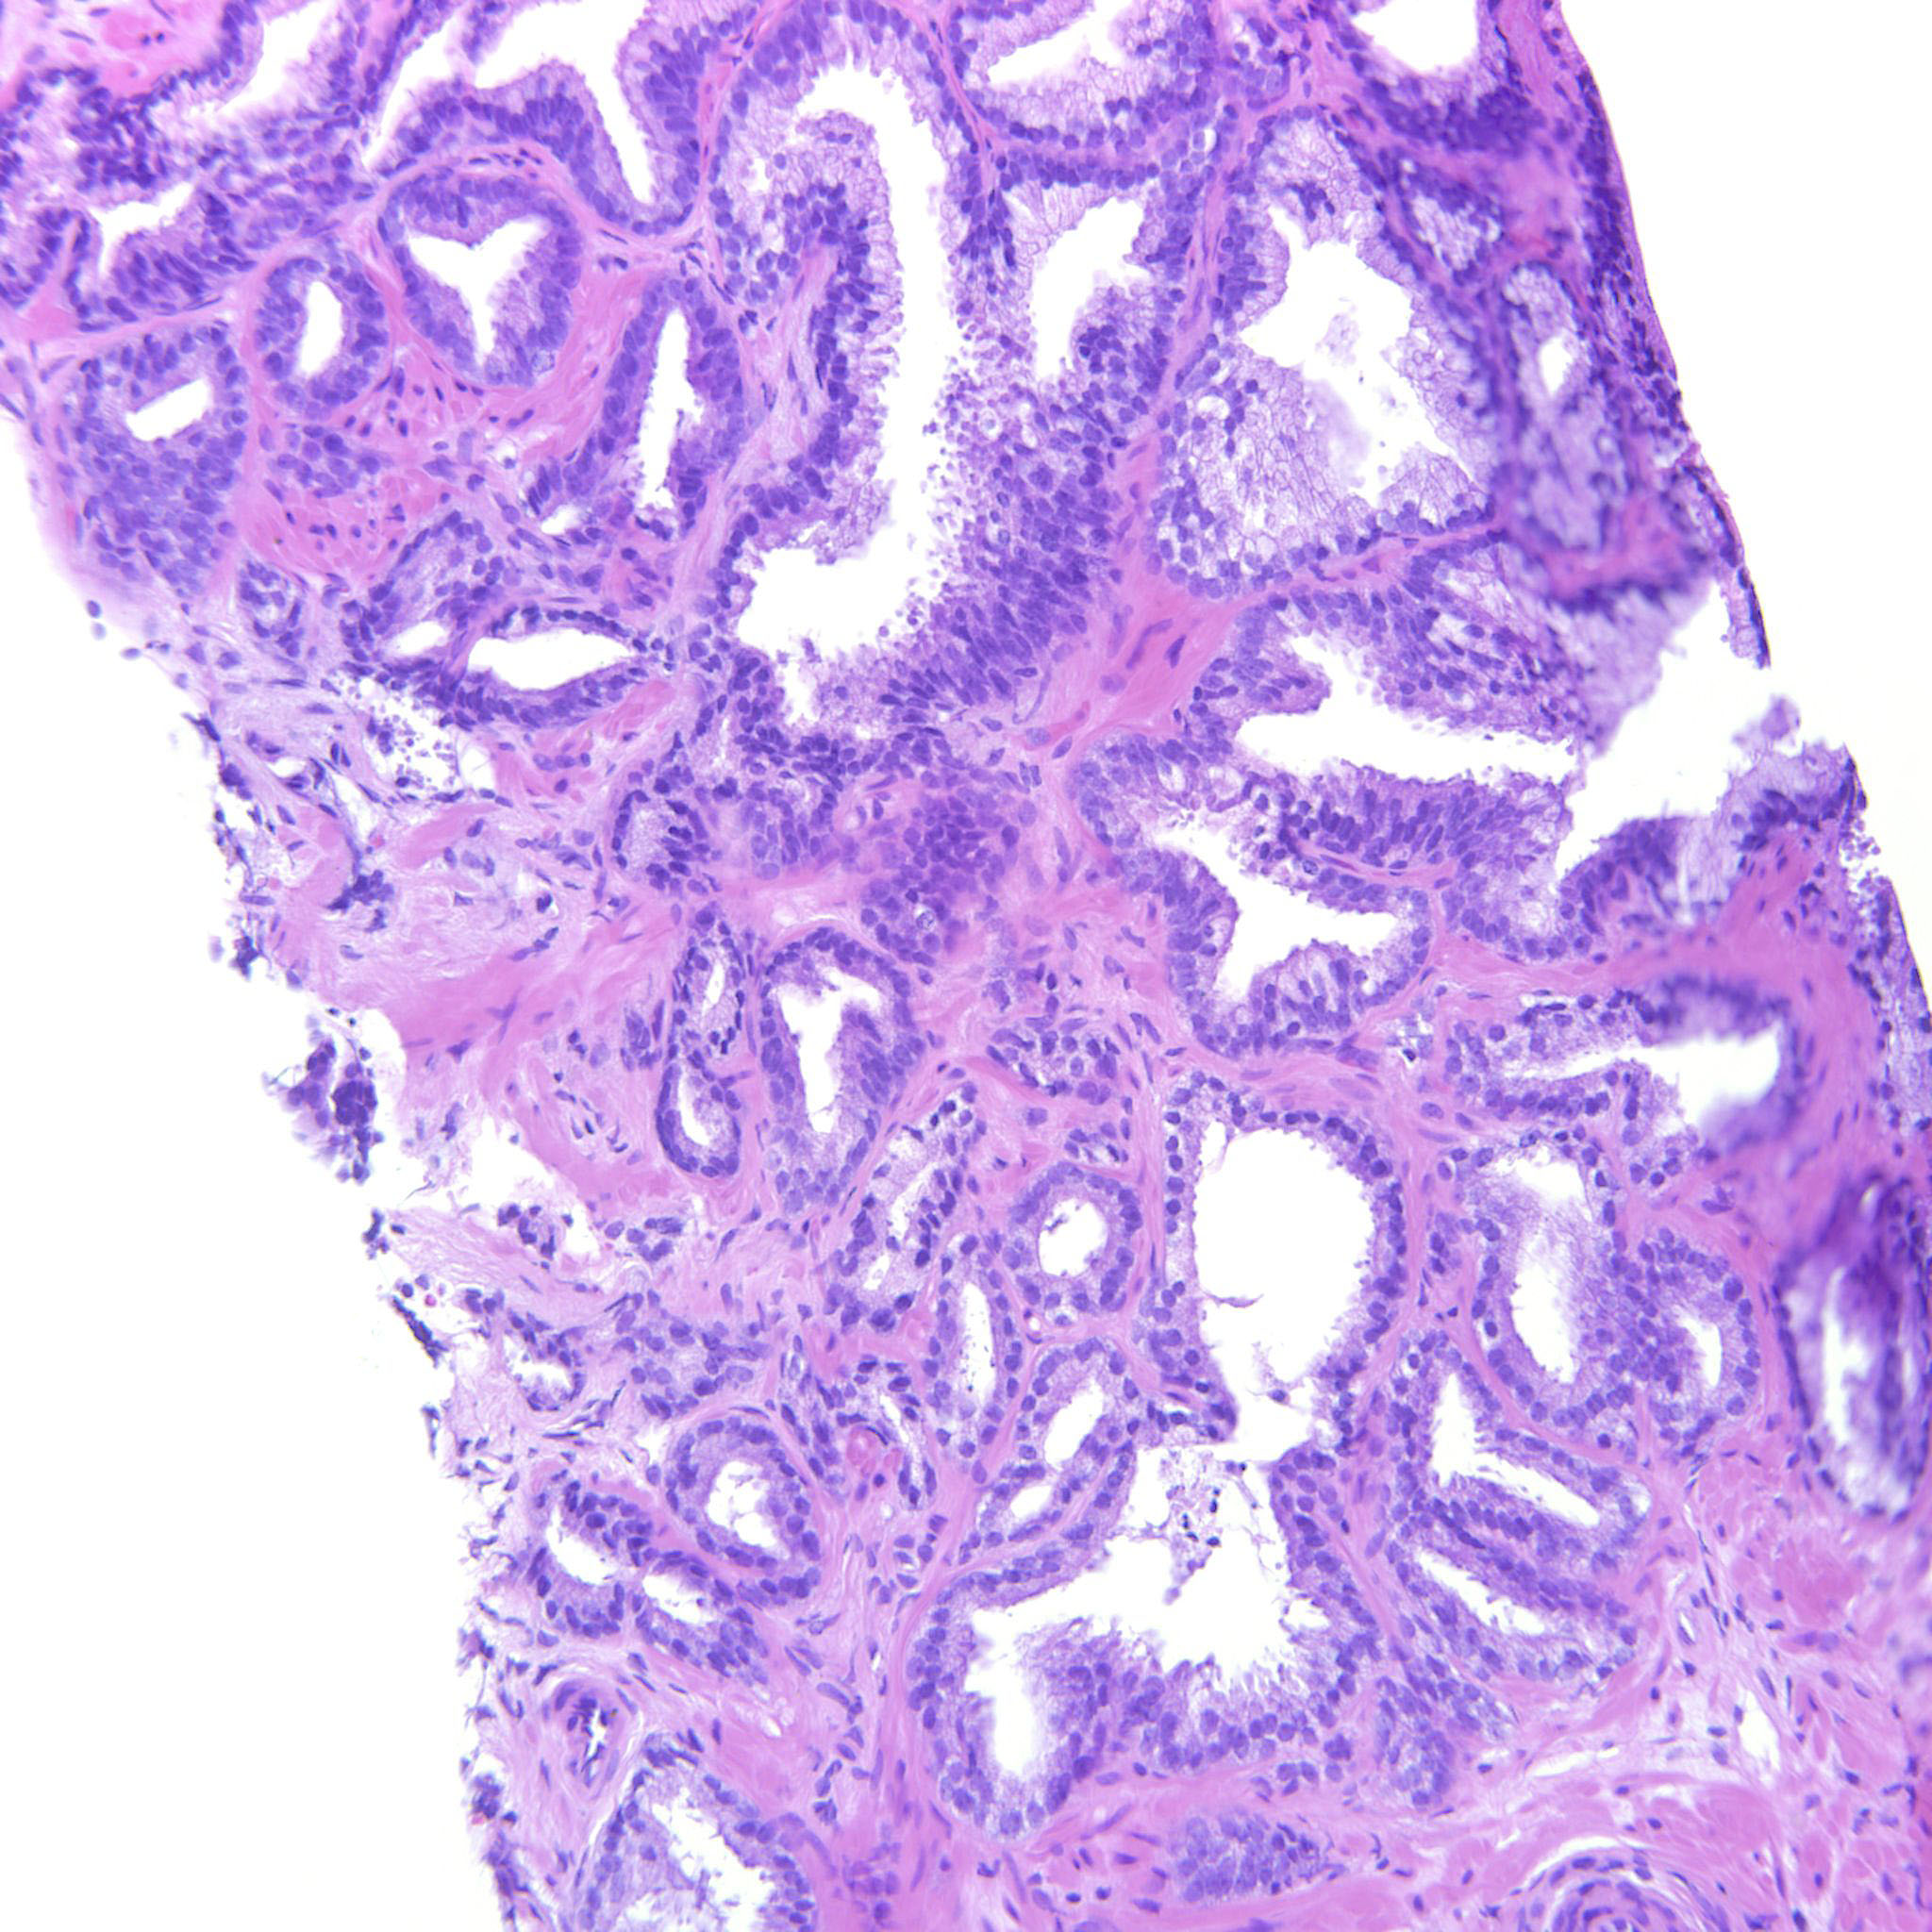

Prostate cancer grading

Case ID: 314